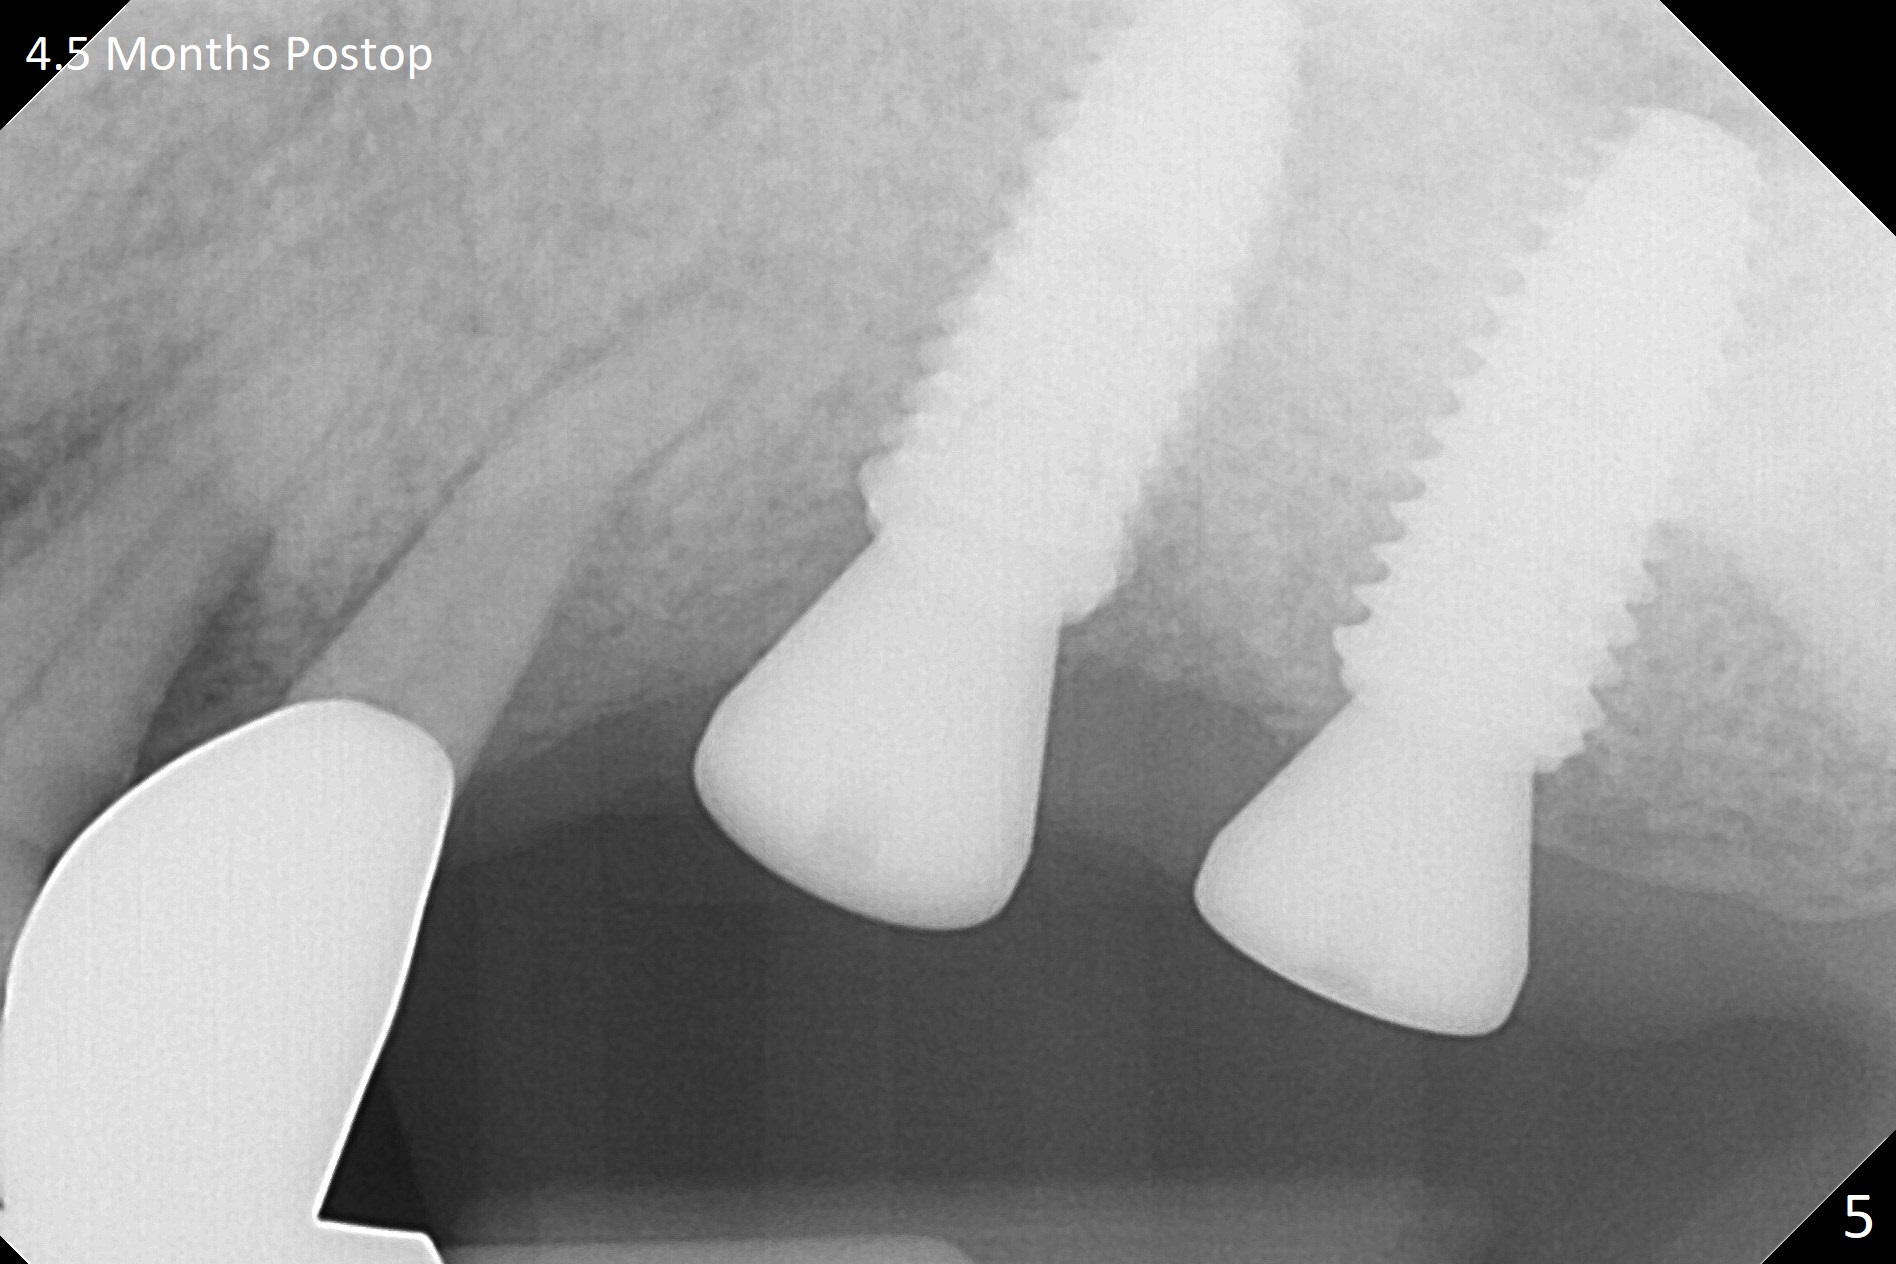

At the time of surgery, there are no 5x10 mm implants in the office for the sites of #14 and 15. Reanalysis of CT shows that there is enough bone for 11.5 mm implants. Before implant placement (Fig.1), there is no perforation of the sinus floor, as shown by probing and nasal blowing test. When a 3.5x11.5 mm implant is placed at #29 in the same appointment, it appears to be supracrestal buccal. Autogenous bone (Fig.2,3 *) is placed in the osteotomy following insertion of a healing screw (S). Periodontal dressing is applied, but it is dislodged after dinner. In fact there is bone coronal to the implant 4.5 months postop (Fig.4), which is confirmed during uncover procedure. There is no abnormality at #14 or 15 4.5 months postop (Fig.5). Impression is taken following extraction of the abnormally shifted opposing tooth #18.